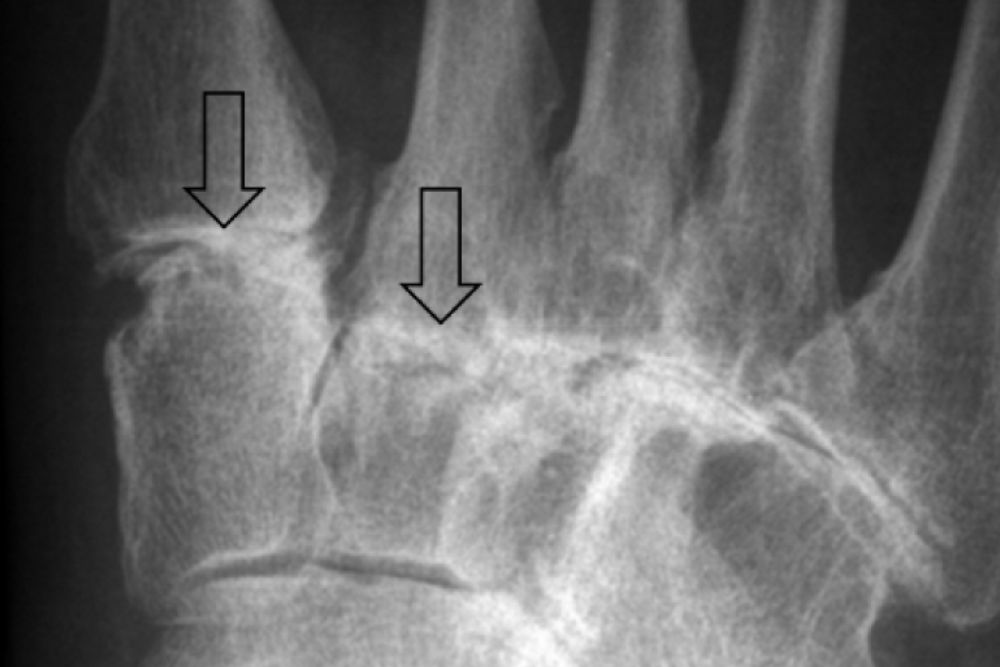

Arthritis can arise from different causes but generally involves damage to the cartilage and articulating surfaces of joints. With many joints in the foot and ankle, all are susceptible to arthritis and its painful effects.